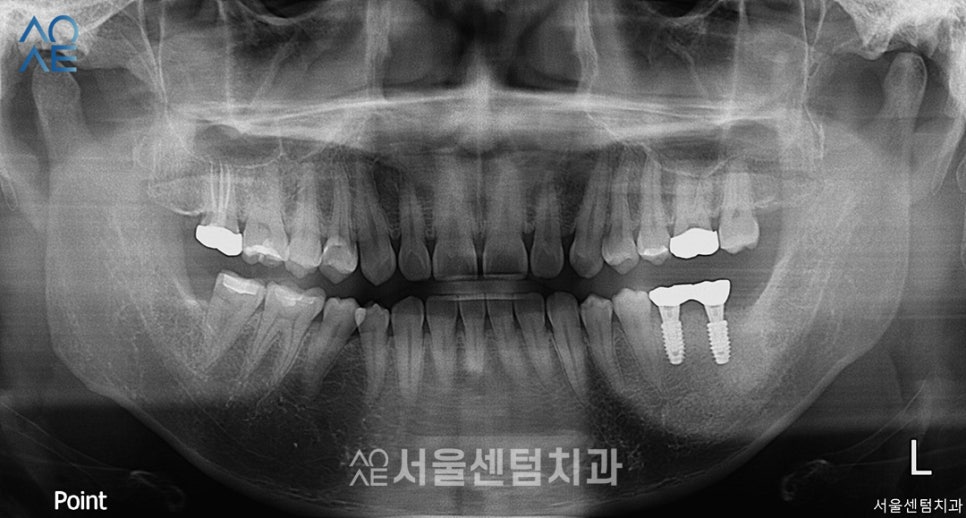

치료가 필요한 치아의 부분에

표시를 해두었습니다.

(사진과 실제 치아는 반대 방향입니다)

| 🦷현재 상태 &치료 계획🦷 |

| (1) 현재 상태🔹 사랑니로 인해 손상된 어금니 있음🔹치아의 절반 이상 충치가 진행된 치아 있음 |

| (2) 치료 계획🔹[오른쪽 위] 어금니 신경치료🔹[왼쪽 아래] 사랑니발치🔹[왼쪽 아래] 임플란트 2개 식립 |